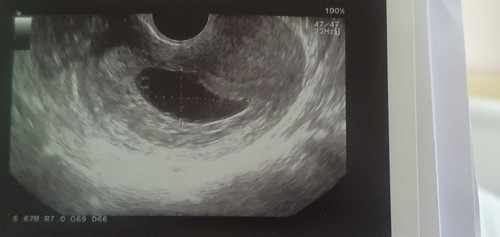

เราอายุ35ปี ท้องแรก มาฝากครรภ์กับรพ. ซาวน์ครั้งแรกตอน6w หมอแจ้งว่าท้องปกติ ท้องในมดลูก ซึ่งวันนั้นก้อไม่ได้บอกนะว่าเด็กมีหัวใจเต้นรึไม่ จนเรา12w มาหาหมอเผื่อเจาะเลือดตรวจโคโมโซม หมอถามว่า ตัวเด้กอายุเท่ารัยเราก้อไม่รู้ หมอจึงให้ซาวน์มาพบว่า ไม่มีเด้กมีแต่ถุงน้ำคร่ำที่ขยายขึ้น และจุดไข่แดง (ก่อนหน้านี้อาการเราเหมืนคนท้องปกติ ไม่เคยมีเลือดออก รึอาการปวดท้องใดๆเลย รวมทั้งเราบำรุง กินโฟเลทก่อนท้องเปนปี จนปัจจุบัน)เคยอ่านเลยท้องลม แต่ไม่คิดว่าจะเกิดกับตัวเอง ตอนนี้เราได้ขูดมดลูกเปนที่เรียบร้อย อยากรุ้ว่ามีคนที่ขูดมดลูกแล้วไม่มีลูกอีกเลยไหม อยากมีลูกมากกัวเค้าจะไม่มาอีก ปล.ไปซาวน์ที่คลินิกอีกรอบเพื่อให้ชัวร์ หมอบอกว่าจิงๆควรจะรุ้ตั้งแต่ซาวน์ครั้งแรกเมื่อ 6w รึรพ.ไม่ดี(รพ.รัฐแถวเสาวรีย์)